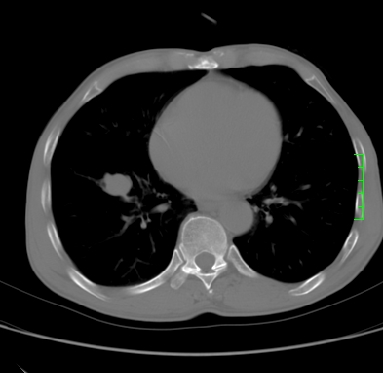

m,73y。膝关节疼痛伴双下肢水肿。入院常规胸片发现结节灶。增强为静脉期。

指套征,强化明显,近侧肺组织局限性肺气肿,考虑支气管类癌,慢支、肺气肿、双上陈旧性tb、冠脉钙化。

1)考虑右肺下叶周围型肺癌。2)右肺上叶及左肺感染性病变(结核可能)。3)肺气肿。4)冠状动脉钙化。